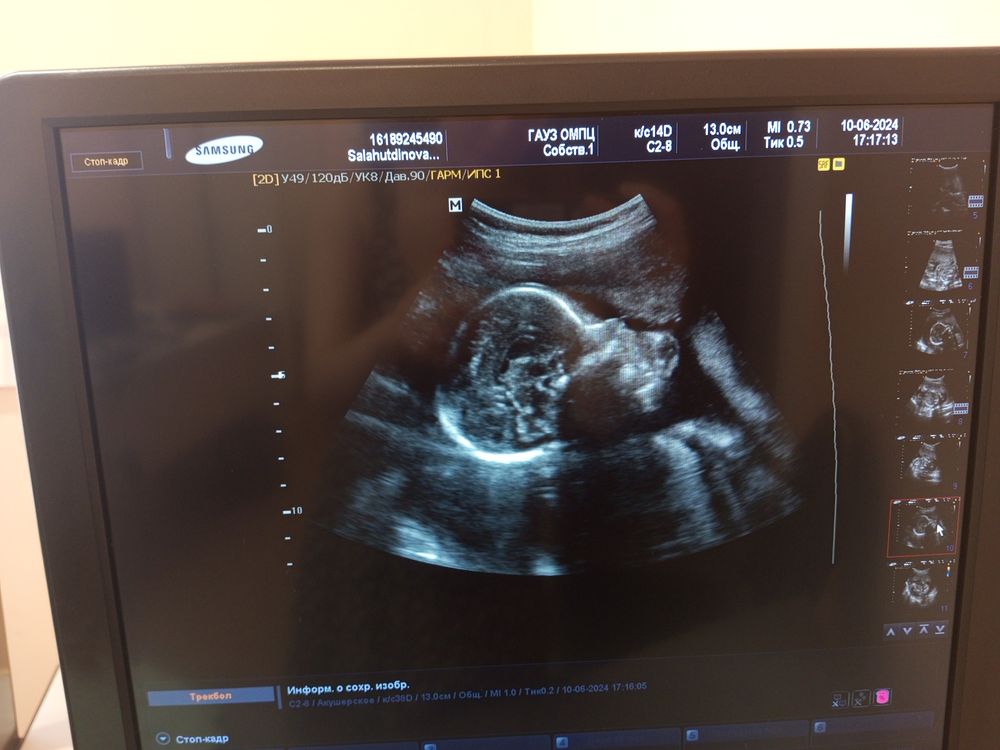

Фото второго скрининга, профиль лица кажется, немного не понимаю, либо она закрылась руками, выглядит будто длинная голова... Да и размер

Одна ручка на переднем фоне, а вторую походу сосет - кулак во рту.

Mari Vest, ну логично: одну ручку хорошо видно всю. А комочек возле рта... Ну что это может быть? На пуповину не похоже... А вот на кулачок похоже - очень характерный жест обсасывания ручки)) Или может вас форма черепа смутила? Вроде обычная голова...)

Просто снимок так получился, картинка ведь размывается от движения датчика и ребенка)